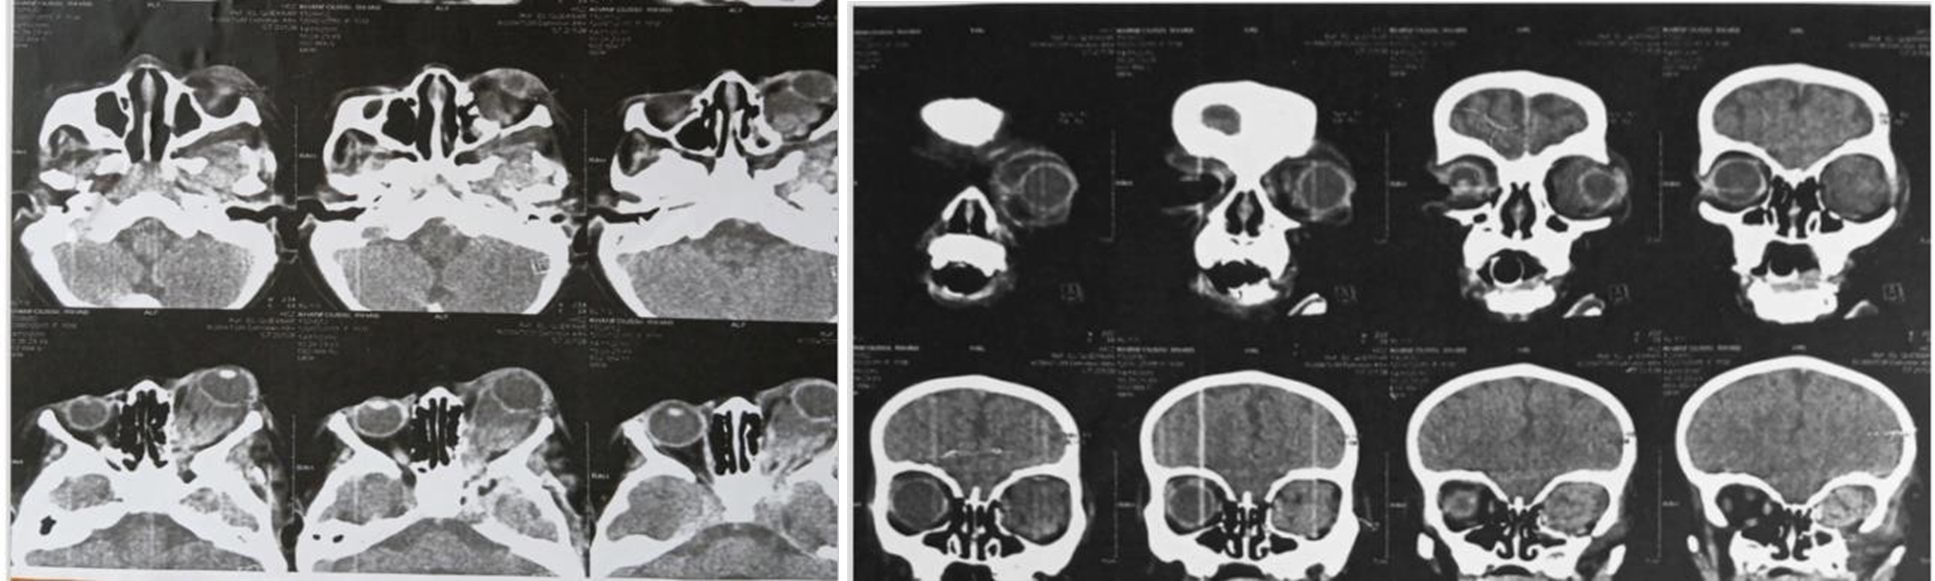

A CT scan revealed a large, heterogeneous, polylobulated, isodense intra- and extraconal orbital lesion on the left side, measuring approximately 25 × 22 × 39 mm. This lesion caused significant proptosis of the left globe, extended into the masticatory space and the palpebral region, and was associated with secondary left hemimandibular dysmorphia (Figure 2).

Figure 2: Large orbital heterogenous lesion in the intraconal space with proptosis of the left globe and hemimandibular dysmorphia.